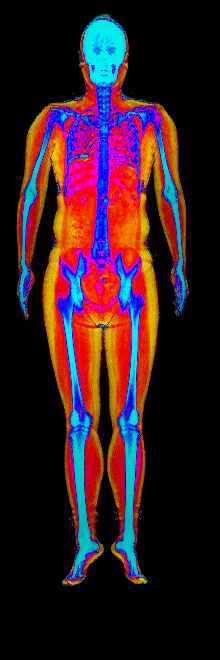

This page features real, anonymized DEXA scan images from BodyStats clients, organized by gender and body fat percentage in 5% increments. DEXA (Dual-Energy X-ray Absorptiometry) is the clinical gold standard for measuring body composition — far more accurate than scales, calipers, or visual estimates.

Each colorized scan shows the distribution of fat tissue (shown in warmer colors) and lean tissue (cooler colors) throughout the body. Compare your own DEXA scan to others in your range, or see what different body fat levels actually look like on a scan.

Female DEXA Scans by Body Fat %

20 to 25% body fat